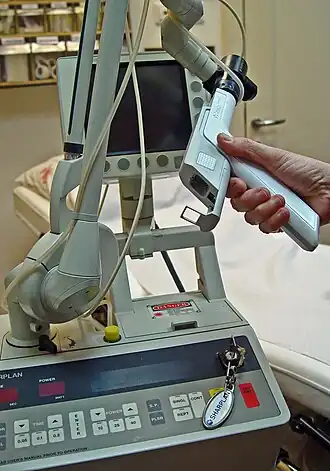

| Electrical cautery |

|

Electrical surgical cauterization utilizes electricity in either a monopolar or bipolar format to burn soft tissue and control bleeding[12] |

|